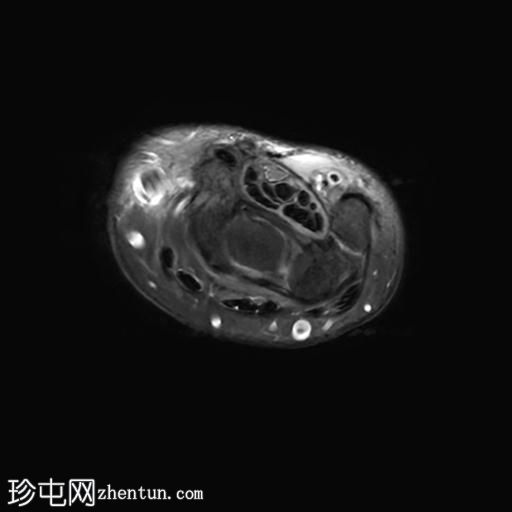

轴向PD值

脂肪饱和度

轴向

T1

MRI显示腕部第一背侧肌腱(拇长展肌和拇短伸肌)增厚,并伴有异常增厚的实质内液体信号。腱鞘内液体增多。

尺侧腕伸肌腱可见异常线性实质内液体信号增多,与板状间质撕裂相关。

MRI表现和临床表现提示De Quervain腱鞘炎。